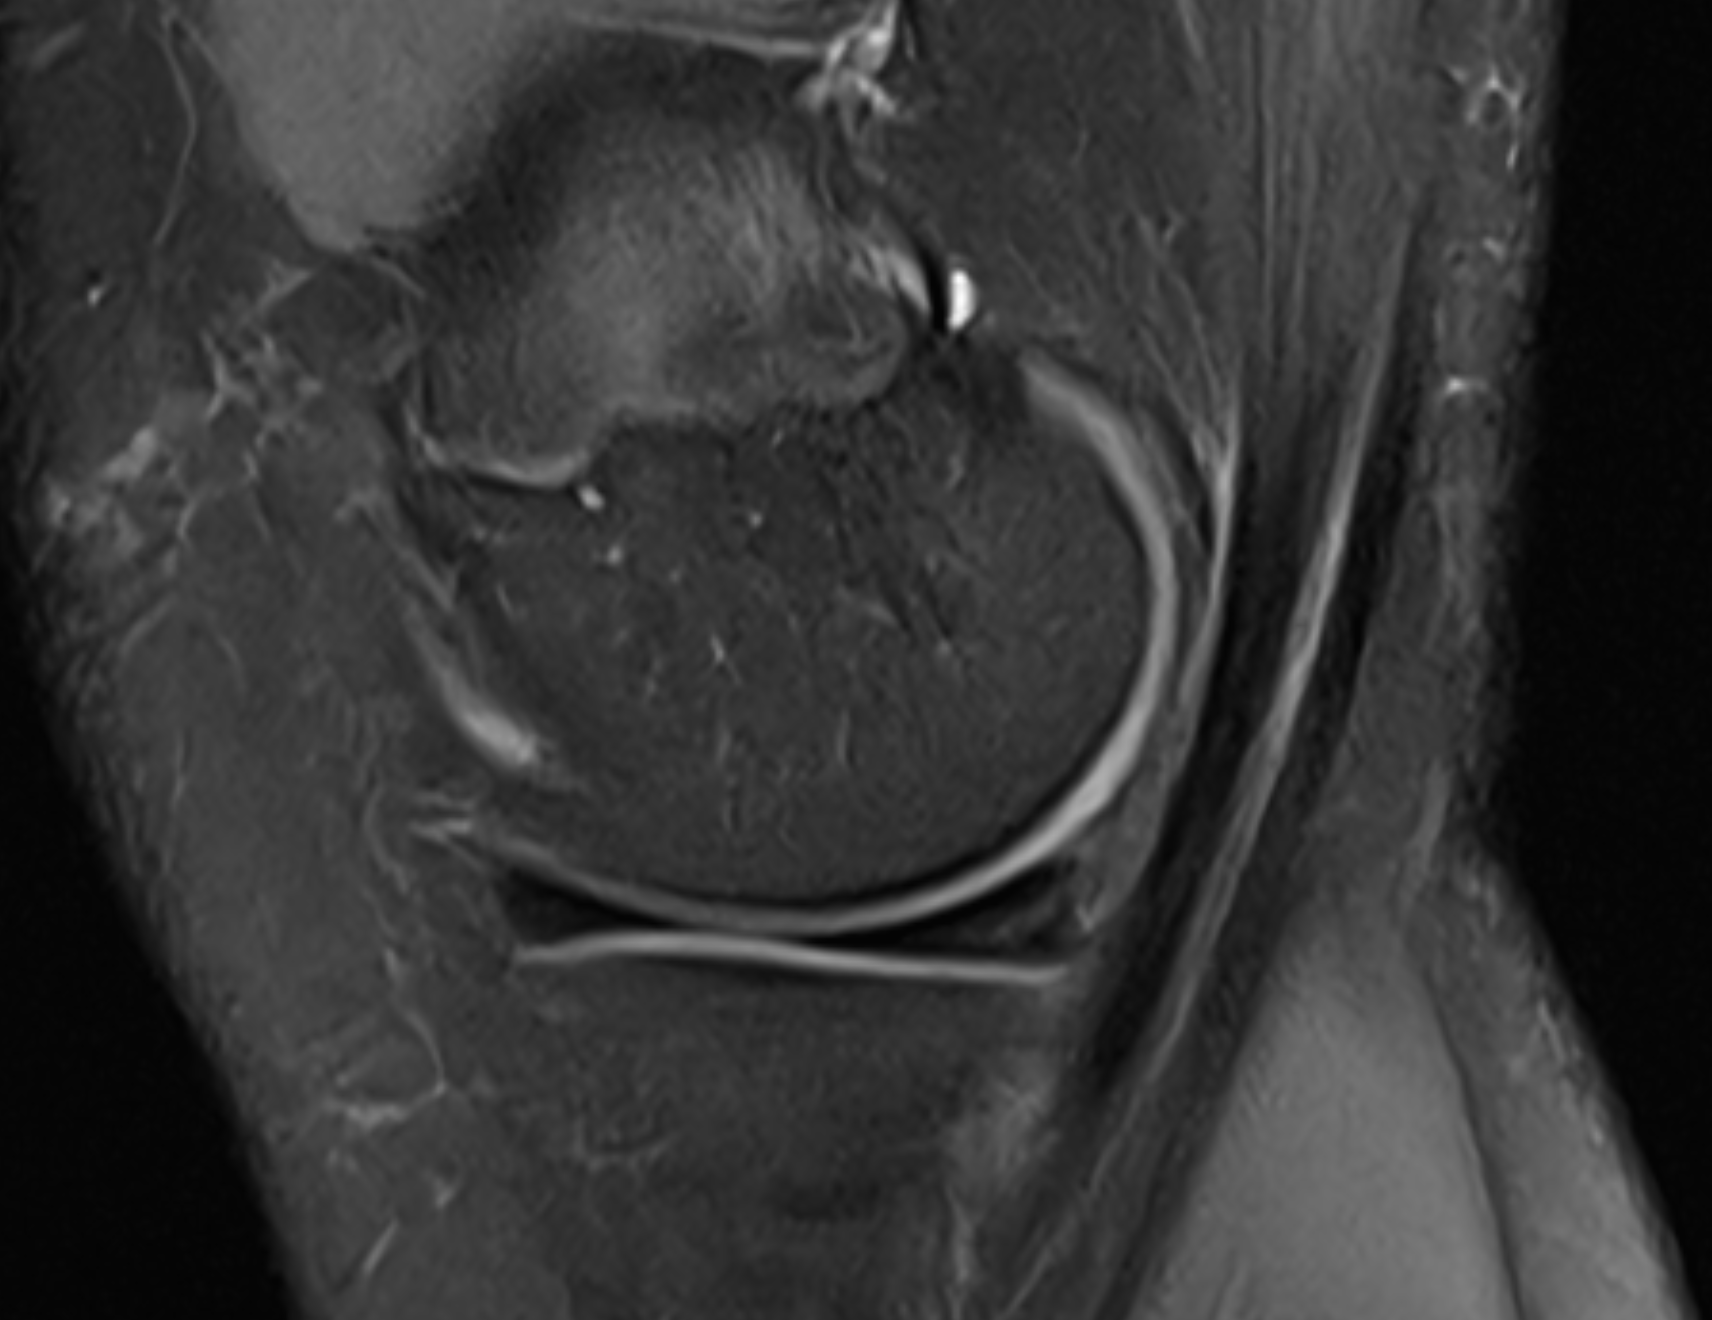

The Double PCL Sign

View: Sagittal (Midline)

Double PCL Sign

What the marker shows: The native Posterior Cruciate Ligament (PCL) is the top dark band. The red marker highlights the second band resting directly beneath it.

This lower band is the torn inner rim of the meniscus that has migrated into the center of the knee joint.